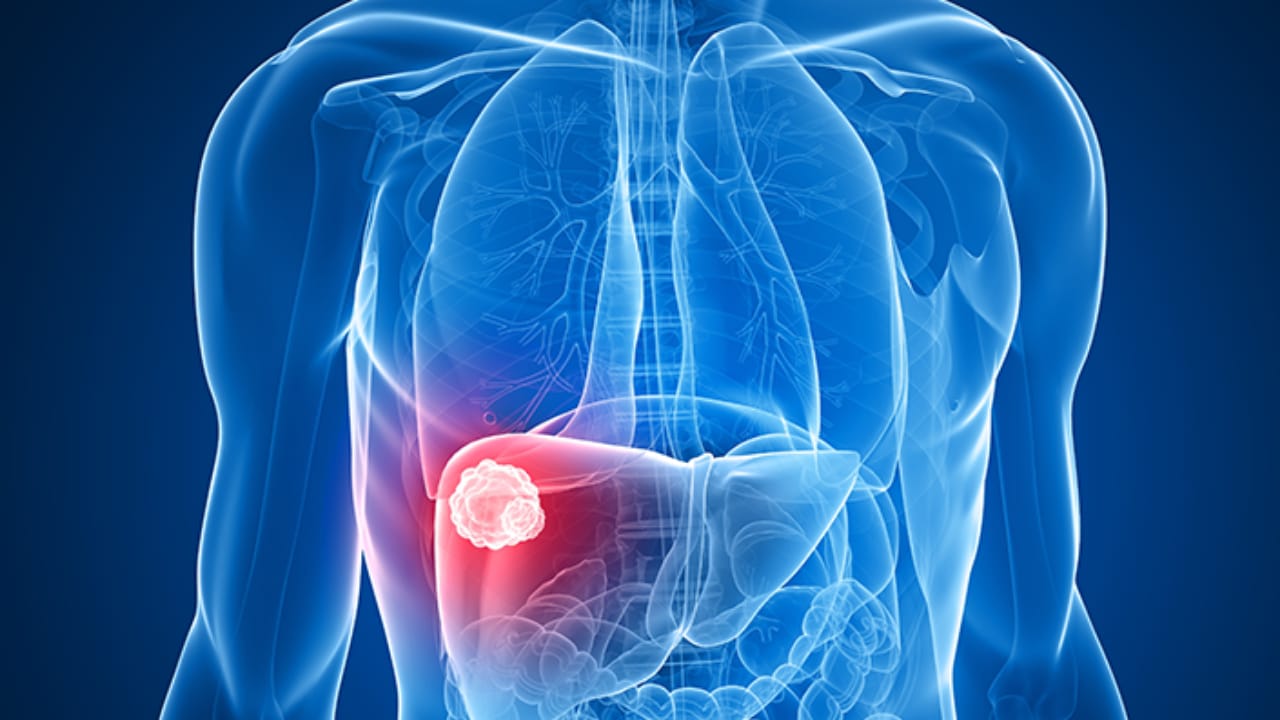

سرطان الكبد

علامات عادية تنبهك بالإصابة بسرطان الكبد

علامات في البطن تشير إلى الإصابة بسرطان الكبد

“القهوة” تخفض خطر الإصابة بسرطان الكبد

دراسة : أواني التيفال تزيد من خطر الإصابة بسرطان الكبد

اكتشاف توليفة من العلاج المناعي تعالج سرطان الكبد

أعراض تشير إلى الإصابة بـ “سرطان الكبد”

أضرار تناول المكسرات منها “الإصابة بسرطان الكبد”

دراسة: الأسبرين يقلل من خطر الإصابة بسرطان الكبد